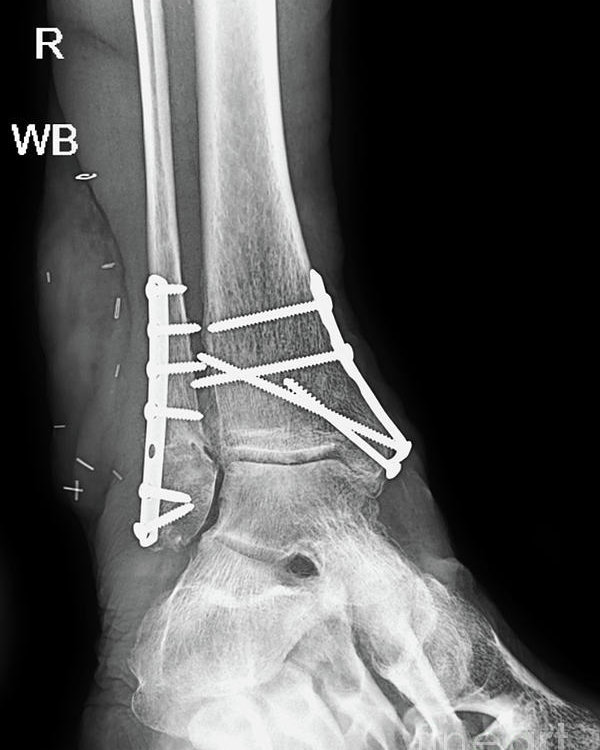

How would you fix articular and comminuted long-bone fracture under ORIF e.g. ankle fracture?

Plate and screws